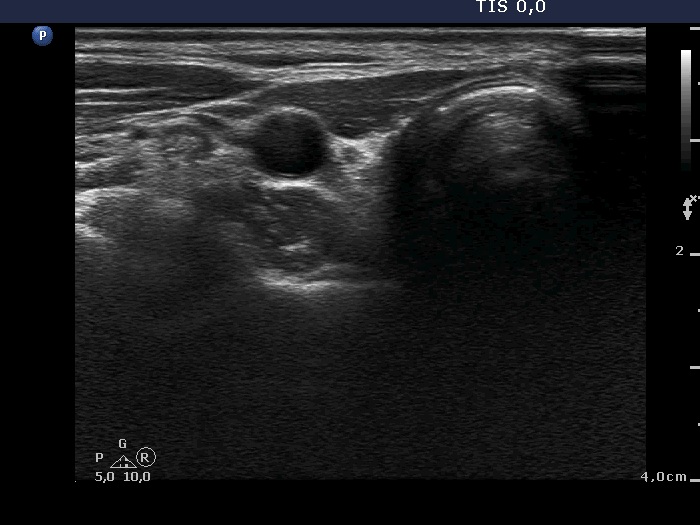

Ultrasound. Connective tissue replaced the thyroid parenchyma in both thyroid beds. There were tiny hypoechoic areas in the right thyroid bed. Two larger hypoechoic lesions were found, one in the isthmus and the other in the left thyroid bed. The latter presented vascularity.

Comment. The presentations of the hypoechoic lesion in all three sites were the same, they differed only in their size. Naturally, the two larger in the isthmus and in the left thyroid bed could cause and did cause concern. Especially that in the left lobe due to its intralesional vascularity. The larger lesions can correspond to small muscle fibers, remnant of the regenerative provess after the surgery but even damaged, non-viable thyroid tissue. Taking the thyroglobulin level into account, the risk of thyroid cancer is minimal but not zero.